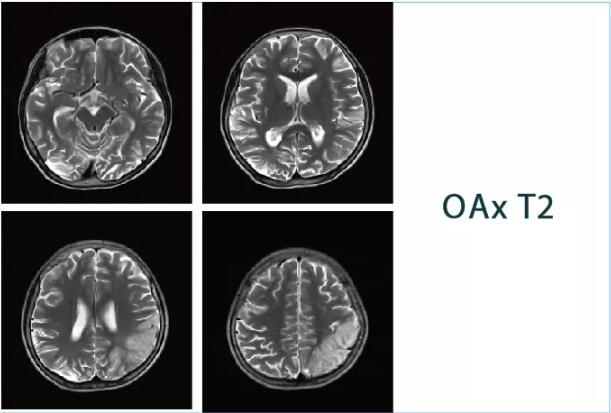

【朗润影像档案】20181026磁共振影像病例结果讨论